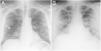

Varón de 48 años con neumonía por COVID-19. A) Radiografía posteroanterior de tórax que muestra opacidades alveolares bilaterales y lineales de distribución periférica (flechas). La puntuación es de 3/6 campos y 4/8 campos, que corresponden a afectación moderada en los tres sistemas 6A, 6B y 8. B) La radiografía anteroposterior realizada 72 horas después muestra un empeoramiento del patrón radiológico con una afectación más extensa y consolidaciones pulmonares. La puntuación es de 5/6 campos y 6/8 campos, que corresponden a afectación grave en sistemas 6A y 6B y moderada en sistema 8.